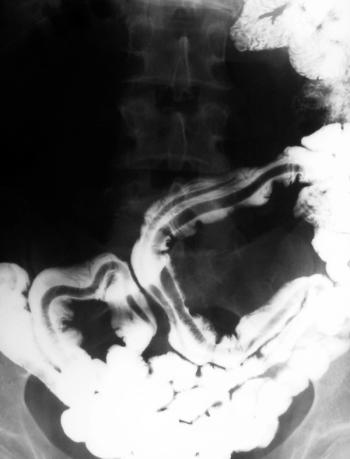

Can you diagnose this patient with unexplained weight loss?